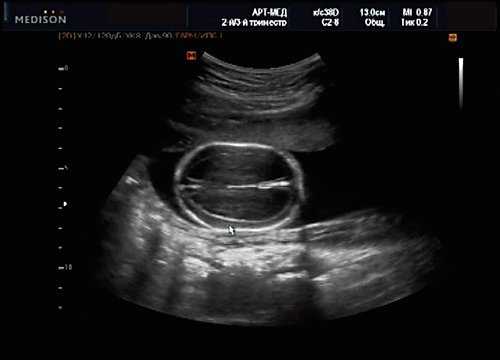

В начале 90-х годов прошлого века в практику был внедрен метод измерения толщины воротникового пространства (ТВП) в I триместре беременности, и к настоящему времени его считают показателем не только анеуплоидии, но и широкого спектра наследственных синдромов и пороков развития [2]. K. Николаидес (K. Nicolaides) с группой исследователей предложили новую модель скрининга на анеуплоидию и установили правила использования этого метода, в частности необходимость применения кривой обучения, проведения аудита, качественного (процедура оценки качества изображений) и количественного (медиана, дельты-ТВП и т.д.). Фонд медицины плода (Fetal Medicine Foundation) стандартизировал предложенный ими клинический протокол и установил правила сертификации для повышения качества медицинской помощи и уменьшения изменчивости результатов данных скрининга [3, 4]. Измерение ТВП можно проводить вручную (рис. 2a) или полуавтоматически (рис. 2b), чтобы результаты измерений были более воспроизводимыми. Кроме того, компания Samsung разработала дополнительный метод измерения показателей ТВП - 5D NT, позволяющий точно выявить срединно-сагиттальную плоскость и улучшить оценки по шкале Германа (Herman score).